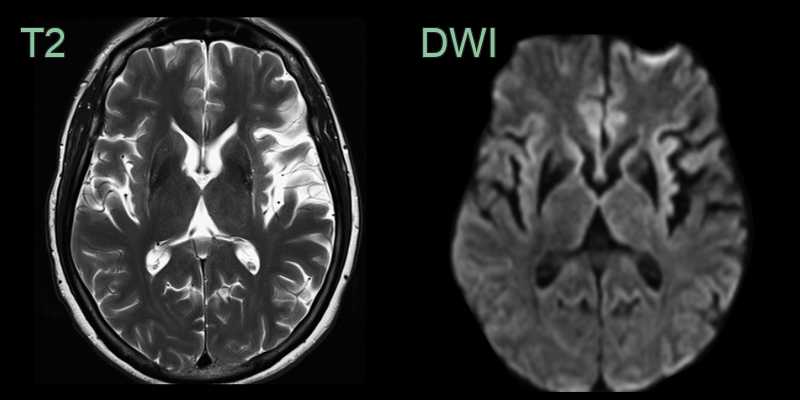

- MRI findings:

- Putaminal atrophy with T2 hypointensity

- "Putaminal rim" sign (T2 hyperintensity at lateral putaminal border)

- 80-year-old patient presented with asymmetric parkinsonism (left > right) with freezing and early falls with poor response to levodopa.

- MRI showed putaminal atrophy, susceptibility artefact and T2-hyperintensity along the lateral aspect of the putamina.